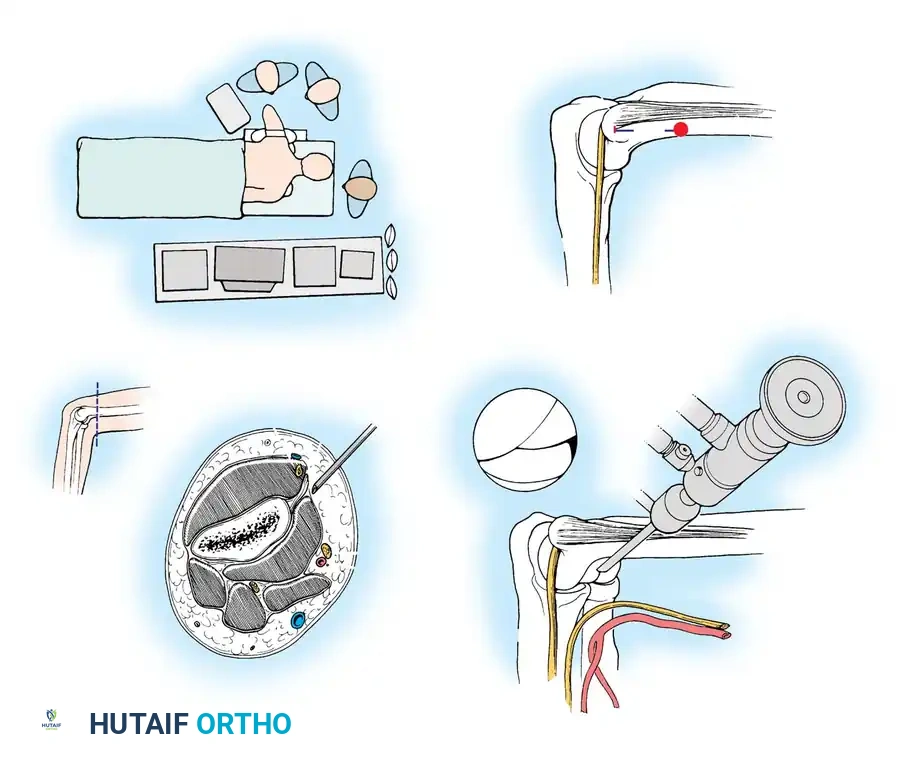

The choice of patient positioning—supine, prone, or lateral decubitus—depends on surgeon preference, the specific pathology being addressed, and the need for airway access. Each position offers distinct biomechanical advantages.

The Supine Suspended Position

With the patient supine, the hand and forearm are placed in a sterile, waterproof stockinette suspension device. This is connected to a rope and pulley system utilizing 5 to 6 lbs of weight to provide balanced suspension.

The patient is positioned so the arm hangs free off the side of the operating table. The shoulder is placed in neutral rotation and 90 degrees of abduction, while the elbow is flexed at 90 degrees.

Advantages of the Supine Position:

* Provides excellent access to both the medial and lateral sides of the elbow.

* The 90-degree flexion relaxes the anterior neurovascular structures in the antecubital fossa, allowing them to fall away from the joint capsule.

The Carson Modification: To eliminate the need for an overhead suspension system, Carson described utilizing two small arm boards placed side-by-side and attached to the operating table at shoulder level. The arm rests on this platform, and an assistant supports the hand upright. This stabilizes the elbow, preventing it from swinging in space, while the narrowness of the boards ensures unobstructed maneuvering of the arthroscope.

The Prone Position

Introduced by Poehling et al. in 1989, the prone position is favored by many advanced elbow arthroscopists.

The patient is placed prone on chest rolls to ensure adequate ventilation. A tourniquet is applied around the proximal arm. An arm board is placed parallel to the operating table, and the shoulder and proximal arm are elevated on a sandbag. The arm is positioned with the shoulder in neutral rotation and 90 degrees of abduction, with the elbow flexed 90 degrees so the hand points directly toward the floor.

Advantages of the Prone Position:

* Improves arthroscopic mobility and makes joint manipulation highly ergonomic.

* Provides superior access to the posterior aspect of the joint (olecranon fossa).

* Gravity assists in pulling the anterior neurovascular structures further away from the anterior capsule, enhancing safety during anterior portal placement.

The surgeon stands with the operating table elevated to chest level to prevent contamination of the dependent hand.

The Lateral Decubitus Position

Developed as a modification of the prone position, the lateral decubitus setup allows excellent access to the posterior compartment while maintaining easier airway access for the anesthesiologist.

The patient is stabilized in the lateral decubitus position using a beanbag and kidney rest. The arm is placed over a bolster attached to the bed. This bolster must be small enough to remain out of the operative field, allowing the elbow to hang freely at 90 degrees of flexion with unobstructed access to all portals. While Takahashi et al. advocated for continuous traction to assist in joint visualization, manual distraction by an assistant is often sufficient to improve exposure.